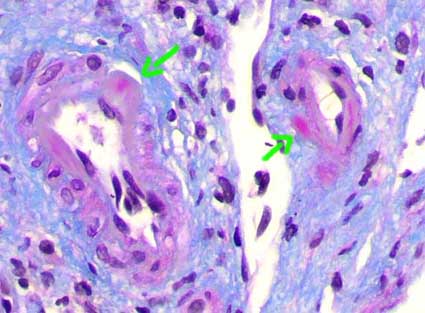

Glomerulopatía crónica del trasplante: Se caracteriza morfológicamente por dobles contornos en las paredes capilares. Esta lesión se debe a síntesis de material similar al de la MBG, en su parte interna y con interposición de células en muchos de los casos. Su patogénesis no está clara; parece que una agresión inmune repetida o continua al endotelio capilar genera, de alguna manera, este cambio. Se gradúa de acuerdo a su extensión en los glomérulos más severamente afectados (Tabla 11). Esta lesión se considera ahora asociada (o debida a) rechazo crónico mediado por anticuerpos (Solez K, et al. Am J Transplant 7:518-526 [Abstract link])

Figura 15. La glomerulopatía crónica del trasplante es uno de los marcadores histológicos que sugiere rechazo crónico (mediado por anticuerpos). Se caracteriza por imágenes en doble contorno de las paredes capilares (flechas). Podemos ver aspecto irregular de la MBG y células mesangiales interpuestas entre estos dos contornos. Esta lesión se gradúa, de acuerdo al esquema de Banff, según la extensión del comrpomiso en los glomérulos más afectados (Tabla 8). (Plata-metenamina, X400).